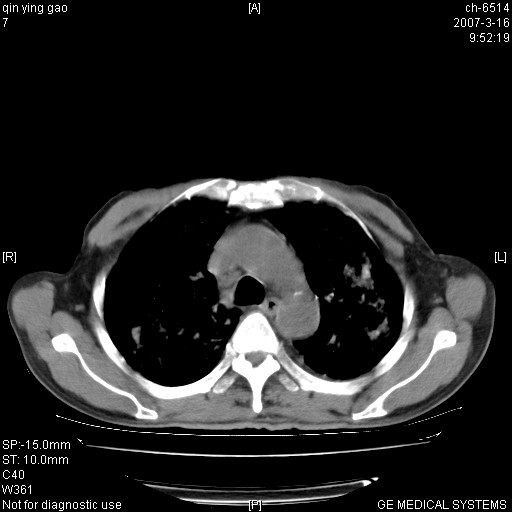

男,64岁.乏力2个月,畏寒、发热1月余。体重下降。血沉加快,白细胞不高。

双肺可见大小不等结节状密度增高影,密度不均,分布不均(双肺上叶为著),亚急性血行播散性肺结核.

(本例特征:以大小不等结节为主,主要分布在双上肺,并部分病灶融合成较大结节,期间搀杂诸多细小结节。从病灶特点与分布形式分析,更趋向于感染。)

两肺弥漫分布的斑片状影,部分融合,左肺及纵隔淋巴结见钙化影,考虑1。tb,2。肺泡细胞癌,建议查痰检

中上肺野密布棉团状影,以胸膜下区为界,边缘模糊,可能是小叶或腺泡渗出及实变。全肺野弥漫分布网线样影及细小粟粒样影,可能是细支气管炎及间质内炎症。综合分析应首先考虑气道播散性感染,而肺内多处斑点性钙化,强烈提示陈旧结核复发并支气管播散。建议详细讯问病史

病变以两肺上野为著,部分病灶有钙化,纵隔窗显示病灶有新老不一,这个首先和结核脱不了干系,还有部分病灶有融洽的倾向,肿瘤也不能完全排出